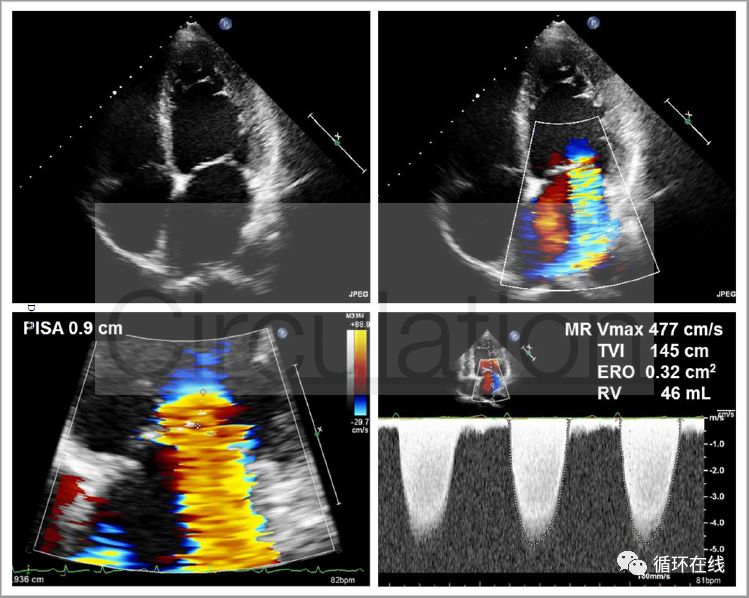

图7(A):基线超声心动图显示重度功能性MR.采用PISA半径和MR射流的峰值速度计算